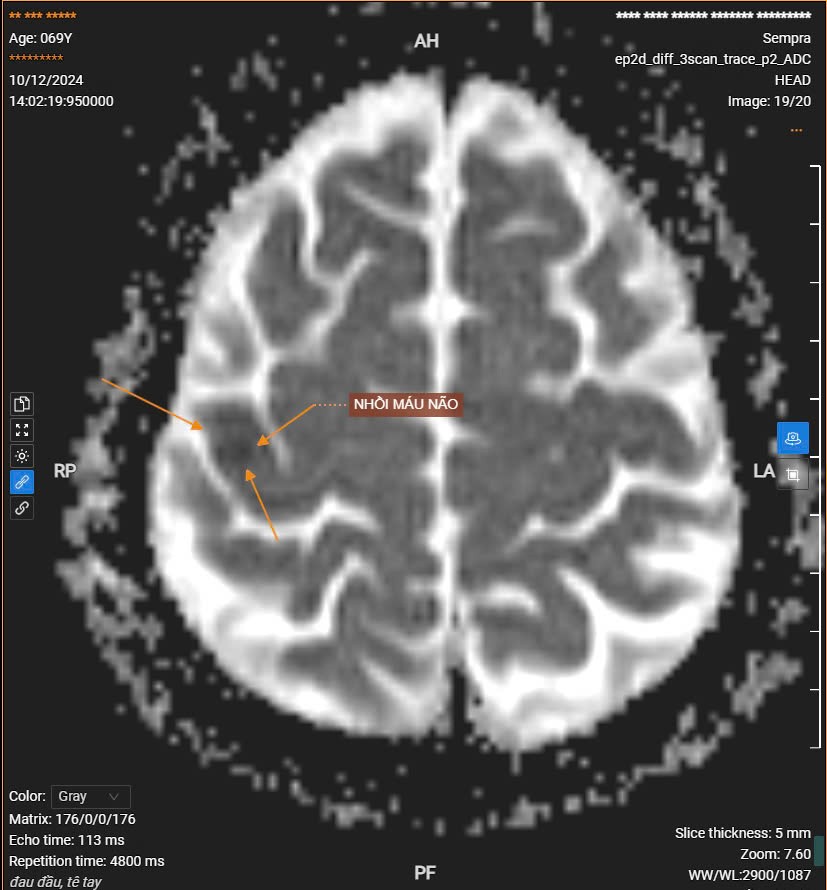

Cẩn trọng với nguy cơ đột quỵ trong mùa đông Thời tiết giá rét mùa đông tại miền Bắc làm gia tăng nguy cơ mắc nhiều bệnh lý, trong đó 2 bệnh đặc biệt nguy hiểm là đột quỵ não và nhồi máu cơ tim.

Ngày 13/12/2024 Bệnh viện Thái Bình đã tiếp nhận bệnh nhân B.T.T 71 tuổi, đến khám với triệu chứng, đau ngực, tăng huyết áp, đau đầu âm ỉ